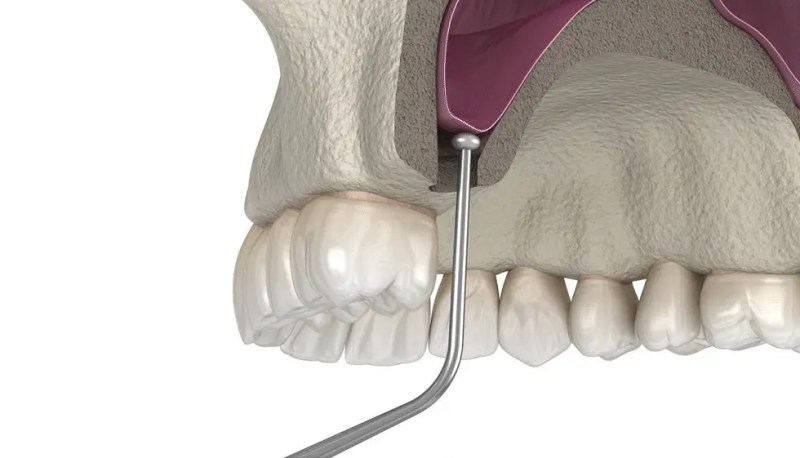

A sinus lift is a surgical procedure that adds bone to your upper jaw in the area of your molars and premolars. It is performed when there is not enough bone in the jaw area to support a dental implant, and the patient has suffered from bone loss due to tooth loss, periodontal disease, congenitally missing teeth, and trauma to the mouth.

Your sinuses are on either side of your nose and above your mouth. When you lose teeth, the bone in that area starts to deteriorate or shrink. This often causes a pocket to develop underneath the root of your tooth, which can lead to tooth loss. At Dr G Dental Studio, we perform a sinus lift to build up the bone in this area to prevent bone loss and a resulting tooth root infection. Bone loss in this area can typically be corrected with a dental implant, but before the implants can be placed, the sinus floor must be raised so that the dental implants have adequate room to be implanted.

A sinus lift or sinus augmentation procedure involves grafting bone from the patient’s hip into the upper jaw. The bone graft is inserted between the upper jaw and the maxillary sinuses, the hollow cavities on either side of the nose. Once the graft is in place, it will fuse with the existing bone to create a stable structure firm enough to support dental implants.

Sinus lift allows for the successful placement of dental implants in the posterior maxilla, where the bone height is insufficient due to the proximity of the maxillary sinus. By increasing the bone height, a sinus lift creates a stable foundation for the placement of dental implants, enhancing their longevity and success rate.